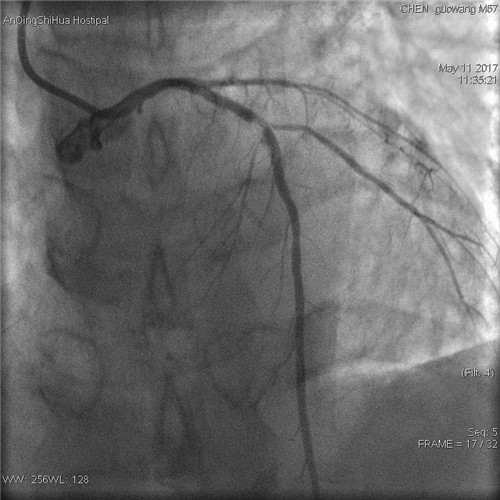

術(shù)前 前降支支架內(nèi)80%局限性再狹窄